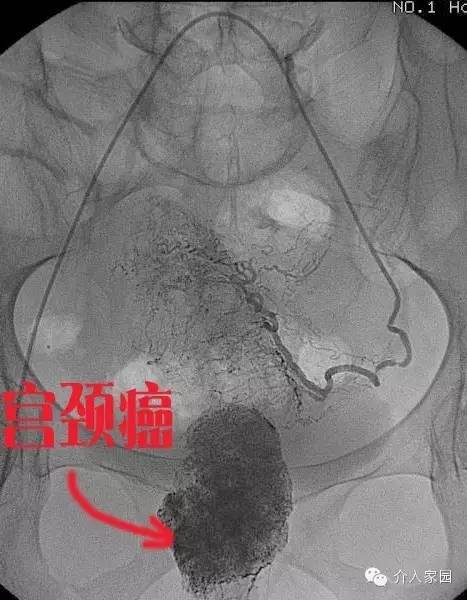

宮頸癌,女性常見腫瘤,也容易導致出血??纯聪旅孢@個病例,由廣州中醫(yī)藥大學一附院介入科提供。這個患者是宮頸癌出現(xiàn)大出血,從下圖造影中我們可以清晰地看到宮頸腫瘤。

下圖是用栓塞劑把整個腫瘤供血堵死后的表現(xiàn),我們可以看到,腫瘤供血消失,患者癥狀也立即得到了好轉(zhuǎn),不再大出血了!